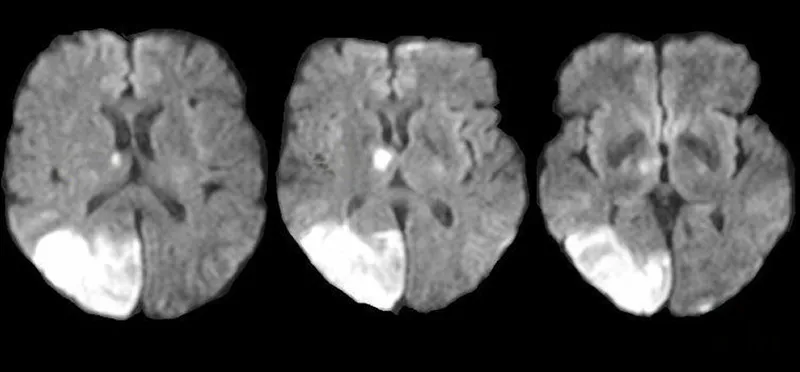

A 69-year-old man is brought in by his wife with acute onset aphasia for the past 5 hours. The patient's wife says that they were sitting having dinner when suddenly he was not able to speak. They delayed coming to the hospital because he had a similar episode 2 months ago which resolved within an hour. His past medical history is significant for hypercholesterolemia, managed with rosuvastatin, and a myocardial infarction (MI) 2 months ago, status post percutaneous transluminal coronary angioplasty complicated by residual angina. His family history is significant for his father who died of MI at age 60. The patient reports a 15-pack-year smoking history but denies any alcohol or recreational drug use. The vital signs include: temperature 37.0℃ (98.6℉), blood pressure 125/85 mm Hg, pulse 96/min, and respiratory rate 19/min. On physical examination, the patient has expressive aphasia. There is a weakness of the right-sided lower facial muscles. The strength in his upper and lower extremities is 4/5 on the right and 5/5 on the left. There is also a decreased sensation on his right side. A noncontrast computed tomography (CT) scan of the head is unremarkable. CT angiography (CTA) and diffusion-weighted magnetic resonance imaging (MRI) of the brain are acquired, and the findings are shown in the exhibit (see image). Which of the following is the best course of treatment in this patient?